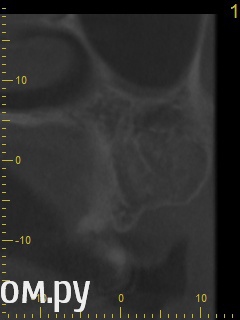

Анатолий М Опубликовано 21 апреля, 2014 Поделиться Опубликовано 21 апреля, 2014 Добрый день. Помогите пожалуйста.17 зуб (верхняя семерка с права). Пол года назад был депульпирован. Все это время присутствуют боли под этим зубом по симптомам очень похожие на кисту (распирание, боль ноющая не сильная, то появляется то сама собой изчезает. при перкуссии 17 зуб слегка болезненный). 2 месяца наза решили зуб перелечить. На ОПТГ ситуация до перелечивания. По снимку видно что первоначальное лечение было проведено плохо. Корни были плохо пройдены и плохо заполены цементом.Месяц хождения с гидроокисью кальция на воде никакого эфекта не дали. Врачи считают что под зубом есть киста. И предлагают удалить зуб. Так как перелечивание не помогло.Прилагаю снимок КЛКТ после лечения. Зуб все еще под временной пломбой. Из трех врачей лишь один разгледел на КЛКТ кисту под 17 зубом. Два других ни на КЛКТ ни на прицельных никакой кисты не видят. Направили к неврологу. Думают что киста если она и есть (в чем они не уверены) не дает имеющихся симптомов.Пожалуйста посмотрите на КЛКТ. Есть ли там киста или нет? И могут ли боли быть от нее?Заранее спасибо. Ссылка на комментарий

red_butler Опубликовано 21 апреля, 2014 Поделиться Опубликовано 21 апреля, 2014 Снимок во время лечения делали? Коффердам и оптика использовались? На кт в тех срезах что Вы выложили кисты не вижу Ссылка на комментарий

Гарриевич Опубликовано 21 апреля, 2014 Поделиться Опубликовано 21 апреля, 2014 Кисты по снимкам нет. Удалять зуб ,по снимкам, причин нет Ссылка на комментарий

DmitrySH Опубликовано 21 апреля, 2014 Поделиться Опубликовано 21 апреля, 2014 Аналогично, никаких признаков воспаления в костной ткани вокруг зуба не увидел. Ссылка на комментарий